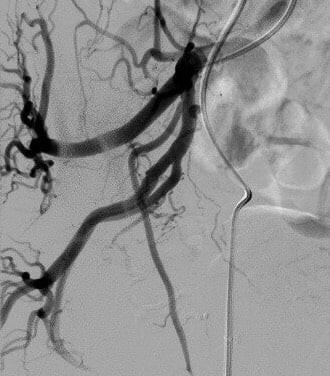

Thời khắc thành công, cả kíp chúng tôi cùng òa lên vui mừng vì đã cứu được bệnh nhân khỏi tình trạng bệnh bí tiểu cấp. Bên cạnh đó, ngay từ khi bắt đầu, chúng tôi đã quyết tâm phải điều trị thật triệt để, giúp cho bệnh nhân đạt hiệu quả cao nhất, không để tái phát. Vì vậy ngoài cách nút tắc động mạch tuyến tiền liệt trong nhu mô bằng hạt thông thường, chúng tôi còn sử dụng keo sinh học để gây tắc hoàn toàn gốc động mạch tuyến tiền liệt hai bên để tránh tái thông nhánh nuôi. Đây là vật liệt khá rẻ nhưng sẵn có, mà hiệu quả điều trị rất cao. Tuy nhiên, khi sử dụng cần bác sĩ rất thành thạo, có kỹ thuật thật tốt để kiểm soát không bị biến chứng cho bệnh nhân, đặc biệt là biến chứng trào ngược gây nhồi máu hoại tử tạng lành như bàng quang và trực tràng. Đây là lần đầu tiên chúng tôi sử dụng kỹ thuật gây tắc “kép” như thế này. Trên y văn thế giới, chúng tôi cũng chưa thấy ghi nhận cách kết hợp độc đáo như vậy.

| Chụp động mạch chậu trong cho thấy động mạch tuyến tiền liệt tách ra từ vị trí khó | Hình ảnh cho thấy động mạch tuyến tiền liệt tách ngay gần động mạch bàng quang trên, dưới đồng thời xoắn 1,5 vòng | Động mạch tuyến tiền liệt sau khi qua được vị trí khó khăn | Chụp mạch kiểm tra lại sau gây tắc hoàn toàn bằng hạt và tắc gốc bằng keo histoacryl |